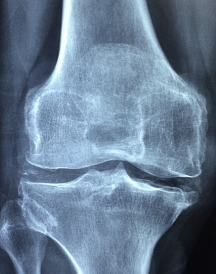

무릎 연골 손상 증상에 대해 알아보겠습니다. 무릎 연골은 무릎 관절의 뼈 사이에 있는 연한 조직으로, 무릎의 충격을 흡수하고 관절의 움직임을 원활하게 해줍니다. 무릎 연골은 외상이나 퇴행성 변화로 인해 손상될 수 있으며, 이 경우 다음과 같은 증상이 나타날 수 있습니다.

무릎 연골 손상 증상은 심각할 수도 있고 그렇지 않을 수도 있습니다. 만약 위와 같은 증상이 지속되거나 악화된다면 의사와 상담하는 것이 좋습니다. 의사는 진단을 위해 병력을 확인하고, 이학적 검사를 하고, MRI 등의 영상 검사를 할 수 있습니다. 진단 결과에 따라 치료 방법을 결정할 수 있습니다.